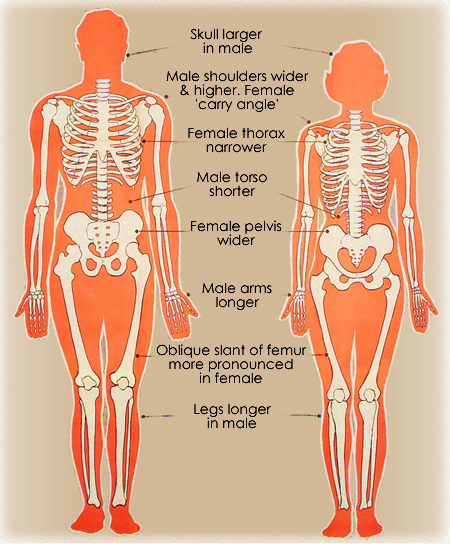

Males have a more pronounced adams apple or thyroid.

And just a general view of the external female genitalia. The following further generalizations have been made regarding male female skeletal differences. The vulva includes the outer and inner lips of the labia labia majora and labia minora clitoris and the openings to the urethra and vagina the whole enchilada.

Female skulls and head bones differ in size and shape from the male skull. The female skeletal system is the most accurate and detailed 3d virtual skeleton available anywhere. The sacrum is connected to the tailbone or coccyx which is made of several fused vertebral bones at the base of the spine.

The ulna is on the medial side of the forearm and forms a hinge joint with the humerus at the elbow. The humerus is the bone of the upper arm. The human body has 206 bones men and women have the same number of bones.

Women tend to have lighter skeleton frames than men. Together they form the part of the pelvis called the pelvic girdle. Bones are not however dead they are living tissue.